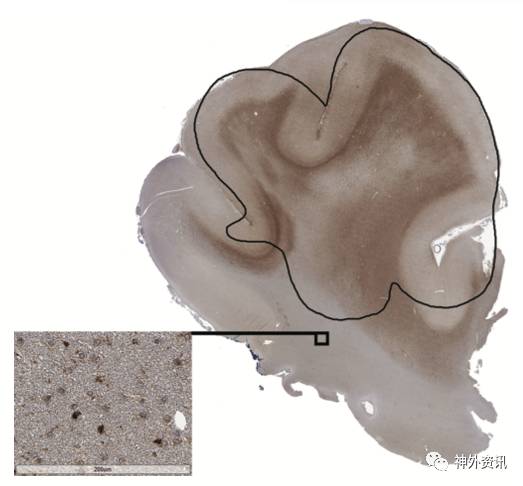

图2. 病例1患者肿瘤周边组织的IDH1染色可见阳性的肿瘤细胞,呈棕色,沿白质纤维束浸润。肿瘤细胞聚集在白质传导束的周围,白质纤维内可见“单排”的肿瘤细胞。放大图提示,影像学显示的肿瘤边界外可见IDH1染色阳性的肿瘤细胞。